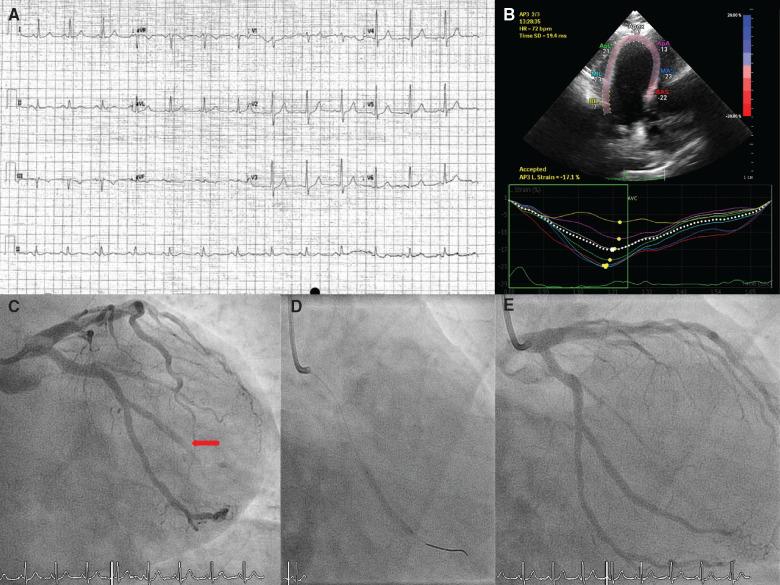

A 49-year-old male with palpitations and manifest pre-excitation was referred for electrophysiology study. Initial study revealed a high-risk left lateral accessory pathway with antegrade effective refractory period of 240 ms and rapidly conducting pre-excited atrial fibrillation. The coronary sinus could not be cannulated to localize the pathway. Coronary angiography and cardiac computed tomography showed an anomalous coronary sinus emptying into the right atrial free wall and patent coronaries. While awaiting repeat electrophysiology study, the patient suffered an acute coronary syndrome with immediate loss of previously visible pre-excitation on electrocardiogram, and underwent stenting of an occluded marginal branch of the circumflex. Repeat electrophysiology study demonstrated a now low-risk accessory pathway (effective refractory period 390 ms). Since infarction, the patient's palpitations have fully settled with all subsequent electrocardiograms devoid of manifest pre-excitation.

Left lateral accessory pathways, which can associate with an anomalous coronary sinus, derive from tissue similar to normal ventricular myocardium and are vulnerable to ischaemic insults in the area subtended by the circumflex artery.